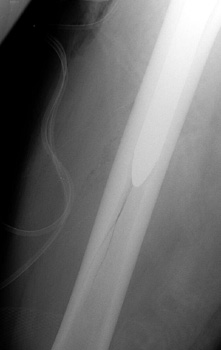

Vascular channel. Linear lucency seen on pre and post operative frog views is vascular channel. These are seen best on the frog leg view, entering the femoral cortex distally and traveling proximally toward the hip into the marrow space.